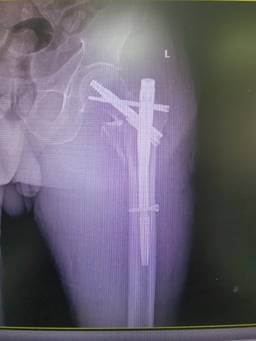

前不久,89歲的廖老因?yàn)樽呗窌r(shí)不小心摔傷左髖部,被緊急送到石化醫(yī)院。X線檢查顯示,廖老的左股骨轉(zhuǎn)子間粉碎性骨折。在完善相關(guān)輔助檢查后,骨科副主任醫(yī)師楊琲、錢立標(biāo)帶領(lǐng)團(tuán)隊(duì)認(rèn)真研究患者影像資料,考慮其基礎(chǔ)疾病較多,有高血壓、糖尿病以及重度骨質(zhì)疏松癥病史,再結(jié)合年齡、病情和康復(fù)鍛煉需要,召集多學(xué)科綜合會(huì)診評估風(fēng)險(xiǎn)。經(jīng)與患者和家屬積極溝通,最終決定運(yùn)用股骨髓內(nèi)釘系統(tǒng)PFBN,為廖老行股骨轉(zhuǎn)子間骨折閉合復(fù)位內(nèi)固定手術(shù)。

手術(shù)當(dāng)日,在麻醉科的協(xié)助下,骨科團(tuán)隊(duì)經(jīng)透視成功將廖老的左髖部牽引復(fù)位,用4個(gè)小切口順利置入PFBN固定,不到40分鐘就成功完成手術(shù)。